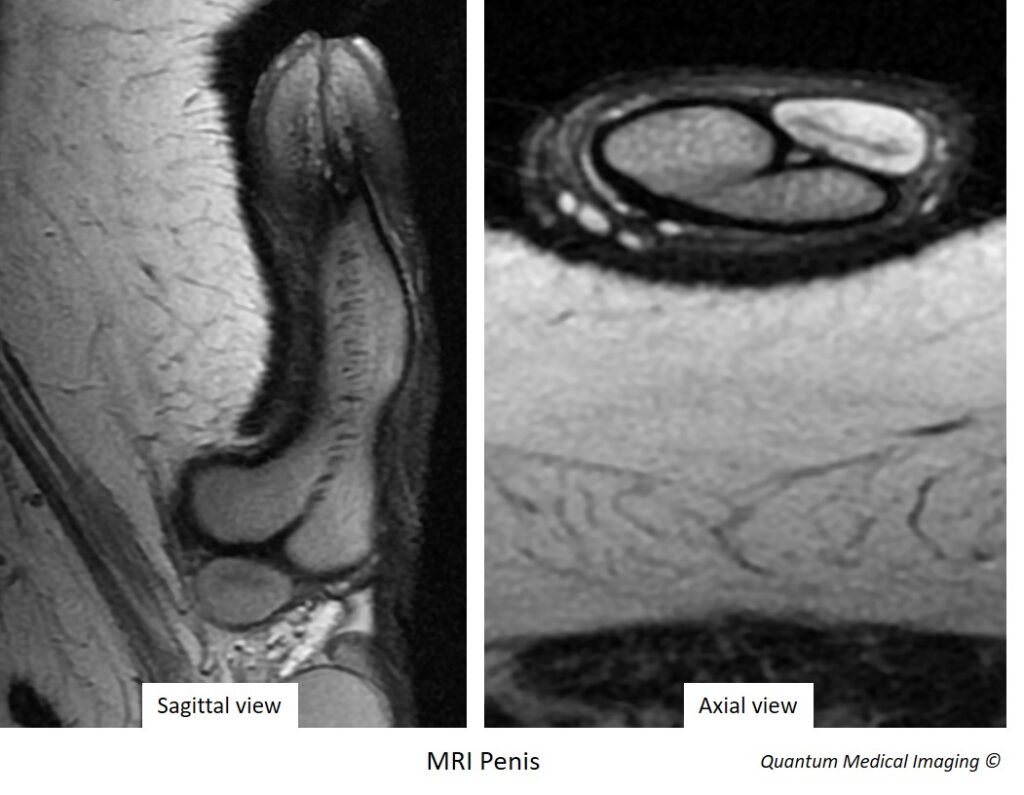

The penis essentially consists of 3 cylindrical bodies – the paired corpora cavernosa and a midline corpus spongiosum on its underside. The corpora cavernosa are composed of special spaces called sinusoids that engorge with blood to form an erection. The corpus spongiosum on the other hand, surrounds the urethra, the latter responsible for ejaculation and urination. Both the corpora cavernosa and corpus spongiosum are enveloped by a strong fibrous capsule known as the tunica albuginea. Like any other organ, the penis too, has its own vasculature, lymphatics and nerves.